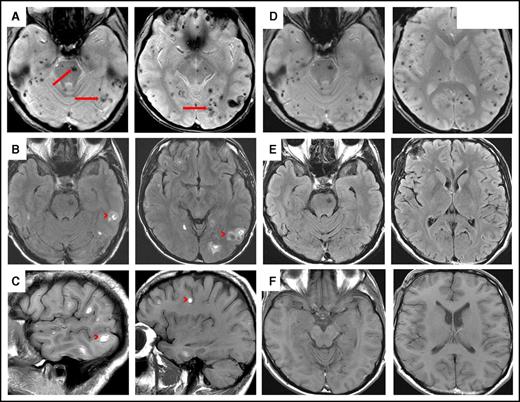

A 42-year-old white man presented with a 4-month history of fatigue, shortness of breath, easy bruising, and headaches. He did not have any significant past medical history, was not hypertensive, and was a nonsmoker who drank alcohol occasionally. He was not taking any medications. There was no family history of hematopoietic neoplasms. Physical examination revealed multiple petechiae and bruising. Neurologic examination revealed no focal neurologic deficits. Cervical, axillary, and inguinal lymph nodes were slightly enlarged. Abdominal examination revealed 18-cm splenomegaly and no hepatomegaly. Computed tomography scanning showed massive splenomegaly with hypoattenuating splenic lesions. Hypoattenuating hepatic lesions and lymphadenopathy in supraclavicular and portal caval lymph nodes were also found. Unenhanced computed tomography scan of the brain revealed multiple hyperdense lesions throughout both hemispheres (not shown). A lumbar puncture and blood cultures showed no evidence of infection, including acid-fast bacilli and Toxoplasma gondii. He was negative for HIV and hepatitis B and C. Magnetic resonance imaging scans of the brain demonstrated multiple small acute hemorrhages at the gray-white junction in the supratentorial and infratentorial brain in axial gradient-echo, axial fluid-attenuated inversion recovery, and sagittal T1 sequences (Figure 1A-C). Radiologic differential diagnosis included hemorrhagic metastases, septic emboli, longstanding severe hypertension, microangiopathy, and vasculitis.

Magnetic resonance imaging of involved brain in HCL before and after chemoimmunotherapy. (A) Axial gradient-echo (GRE) sequence demonstrates innumerable microhemorrhages scattered throughout the supratentorial and infratentorial brain involving both cerebral and cerebellar hemispheres as well as the brainstem (arrows). (B) Axial fluid-attenuated inversion recovery (FLAIR) and (C) sagittal T1 sequences demonstrate multiple small acute hemorrhages at the gray-white junction in the supratentorial and infratentorial brain (these were hyperdense on unenhanced computed tomography scan; not shown) (arrowheads). (D) Axial GRE sequence after chemoimmunotherapy shows multiple microhemorrhages scattered throughout supratentorial and infratentorial brain, consistent with old blood. (E) Axial FLAIR and (F) axial T1 sequences show complete resolution of lesions after chemoimmunotherapy.

Because of the aggressive and unusual clinical presentation with lymphadenopathy, massive splenomegaly, high lymphocyte count, anemia, normal monocyte count, and central nervous system (CNS) involvement, the patient was initially thought to have atypical HCL and was treated with a combination of cladribine (0.14 mg/m2 once per day for 5 days) and rituximab (375 mg/m2 once per week for 8 weeks) per previously published recommendations.9-11 After completion of his treatment, his symptoms, splenomegaly, and lymphadenopathy resolved. The white blood cell count was 4.52 × 109/L; hemoglobin, 128 g/L; platelets, 158 × 109/L; lymphocytes, 0.57 × 109/L; monocytes, 0.39 × 109/L; and neutrophils, 1.48 × 109/L. Six months after completing treatment, the patient was clinically well, and the blood counts and physical examination were normal with the exception of lymphocytopenia (lymphocytes, 0.54 × 109/L); thus, follow-up bone marrow examination was not performed, but flow cytometry of the peripheral blood showed 0.02% cells expressing a hairy cell phenotype. Repeat magnetic resonance imaging scans performed 9 months after completion of therapy showed complete resolution of acute brain lesions in axial fluid-attenuated inversion recovery and axial T1 sequences (Figure 1E-F). Axial gradient-echo sequencing demonstrated multiple microhemorrhages scattered throughout the supratentorial and infratentorial brain, consistent with old blood (Figure 1D).